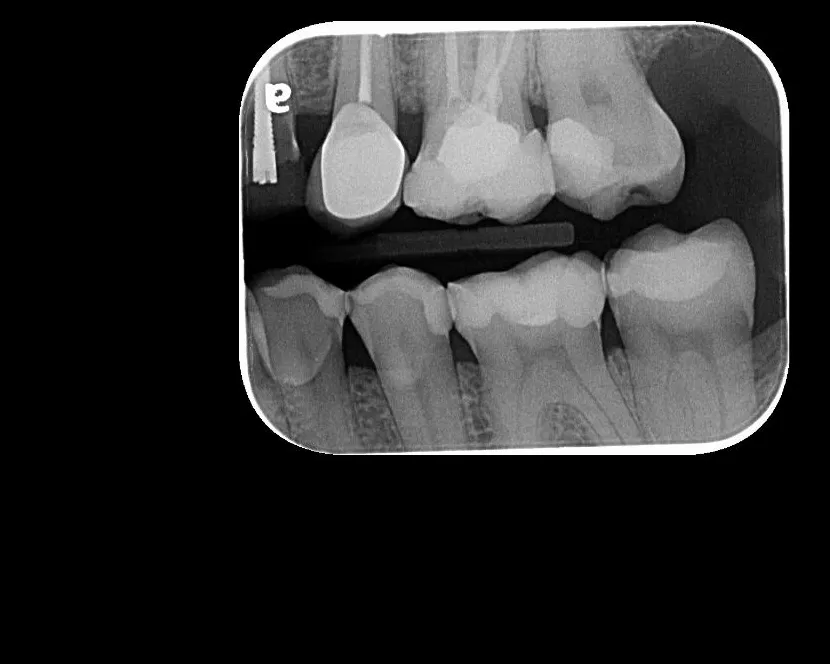

Radiografía Intraoral

La radiografía intraoral permite observar con gran detalle los dientes y las estructuras que los rodean. Es una herramienta fundamental para detectar caries, infecciones, fracturas, alteraciones en la raíz dental o en el hueso de soporte.

• Ideal para tratamientos de endodoncia, implantología y control preventivo.